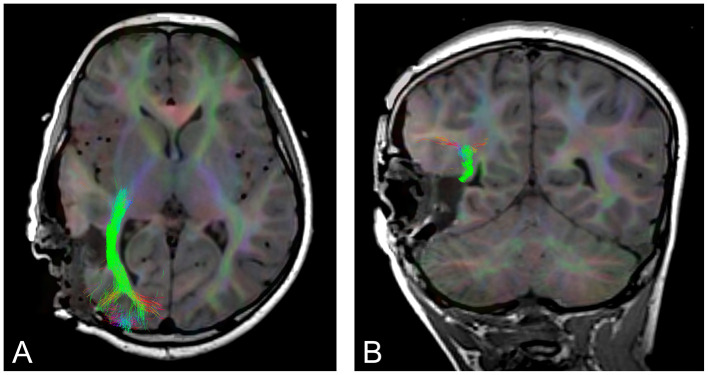

Introduction: Tractography is the only available technique for visualizing whitematter pathways within the living brain. Avoiding these pathways during surgical interventions for brain tumors and epilepsy is key to reducing postoperative neurological deficits whilst achieving maximum safe resection. Despite this, the use of intraoperative tractography is not widely adopted in clinical practice, with time required to run analyses often cited as a limitation. This systematic review and meta-analysis aimed to assess the impact of intraoperative tractography on neurosurgical outcomes in both tumor and epilepsy surgeries.

Results: The search strategy identified 2,611 papers. Following de-duplication and screening, 26 papers were included in the final analysis. Risk of bias was found to be moderate. Findings suggest that the use of intraoperative tractography has the potential to improve surgical outcomes for patients undergoing tumor and epilepsy surgery. Meta-analysis indicated a good rate of gross total resection, 79%, and only three studies of brain tumors and one study of epilepsy reported worsening of neurological deficits.

Discussion: Though the evidence supporting its use remains limited, results indicate that intraoperative tractography can be a valuable tool in improving neurosurgical outcomes and reducing the risk of postoperative deficits. Further research is required to determine optimal use in clinical practice.